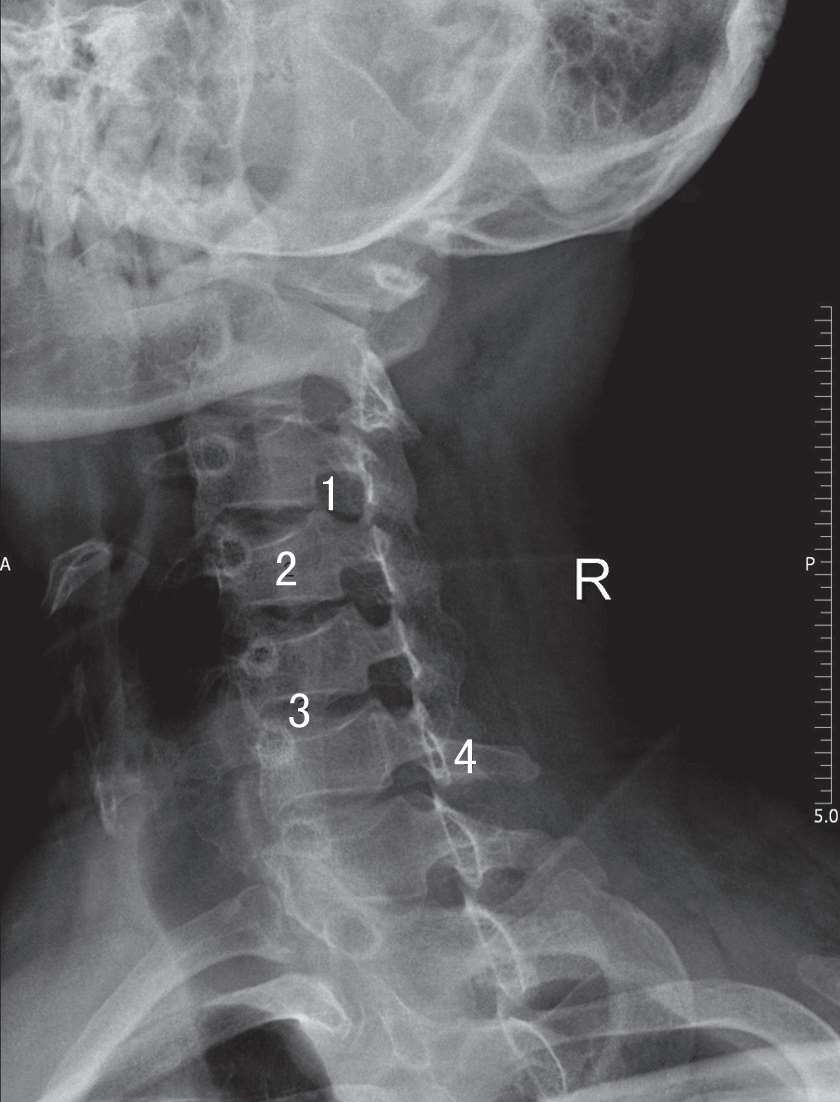

患者取坐位,将患者肩部离开胶片而成为斜位,双肩下垂,冠状面与胶片呈45°,颈椎长轴与胶片长轴平行。胶片上缘抵枕外隆凸,下缘包括颈静脉切迹,颈部斜位中线对胶片长轴中线。中心线向头侧倾斜15°,以甲状软骨为中心射入(图3-7)。椎间孔于斜位片显示清晰,位于椎体与棘突之间,呈椭圆形,左前斜位显示右侧的椎间孔,右前斜位显示左侧的椎间孔(图3-8)。

1. 椎间孔;2.椎体;3. 椎间隙;4. 棘突

图3-8 颈椎斜位X线片